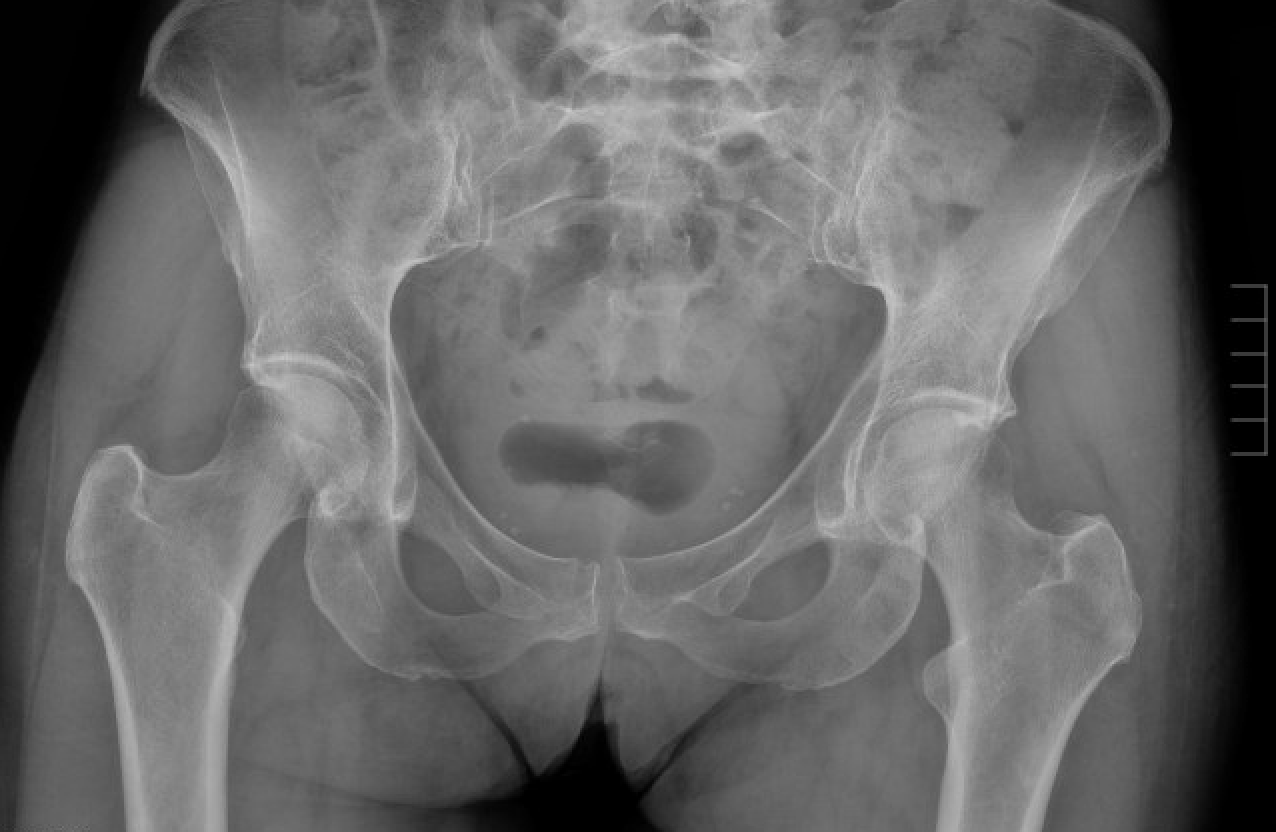

Below is another example of the initial x-rays of a patient who suffered a fall and was unable to walk.

CT later confirmed fractures involving the left acetabulum and ilium, and bilateral pubic rami.